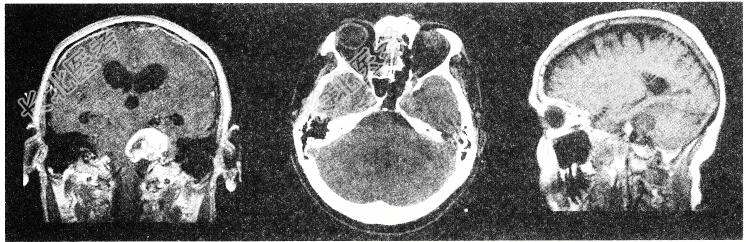

- 单项选择题有关听神经鞘瘤(如图所示)的发生,以下哪项描述不正确

A、听神经瘤起源于Schwann细胞

B、好发于中年人

C、大多数是单侧性

D、听神经瘤多来自耳蜗神经

E、多发生于听神经的内听道段或内耳孔区